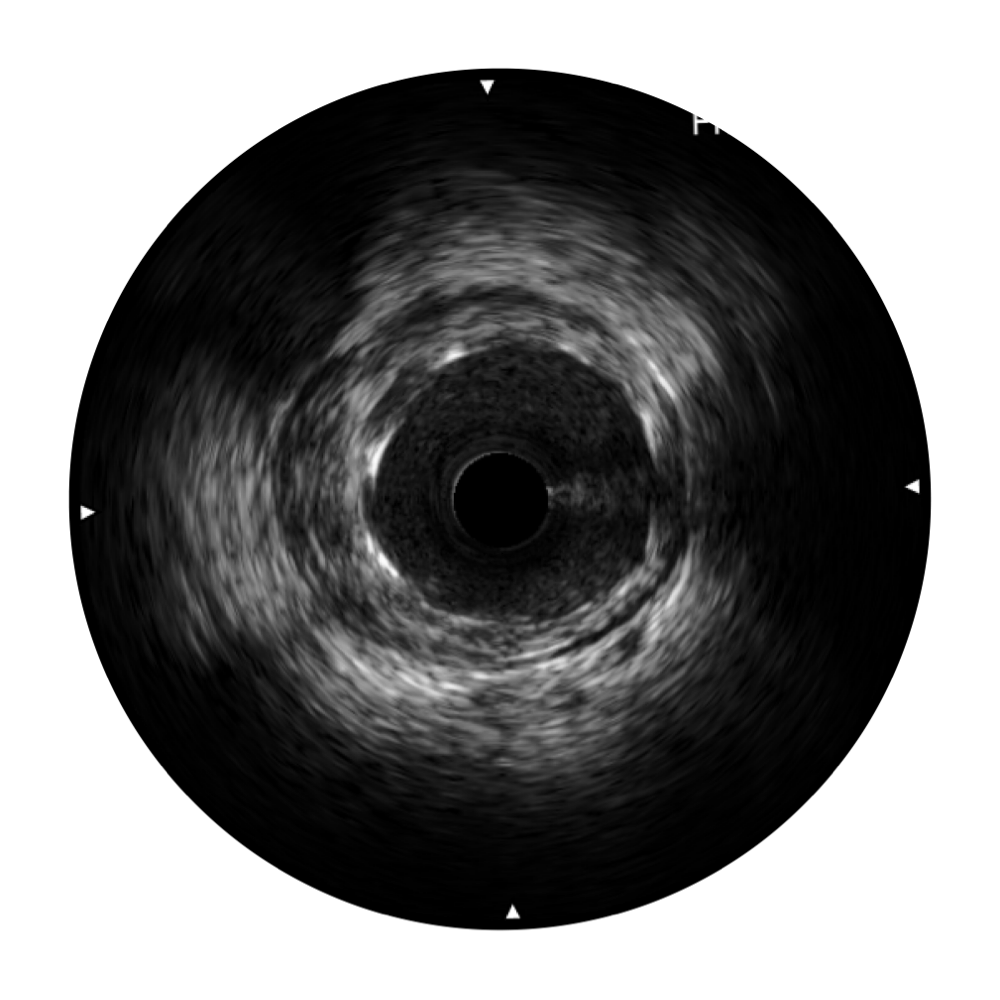

竞技宝(JJB)官方网站宽频IVUS图像

对比传统IVUS导管成像,竞技宝(JJB)官方网站宽频IVUS图像的近场支架梁显影更细腻,远场中膜外血管仍清晰可辨,兼顾远中近,兼顾分辨力与穿透深度